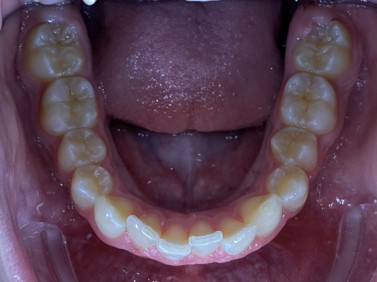

Chief complaint: We present the case of a 12-year-old female patient who came for an orthodontic evaluation, motivated by a family history of treatment. Clinical and radiographic analysis revealed a skeletal Class II malocclusion with molar and canine relationships also in Class II, moderate crowding in both arches, a deviation of the dental midline, and ectopic eruption of tooth 13. No functional issues with breathing or swallowing were observed, and oral health was generally good. A slight mandibular retrusion was noted in the soft tissue profile. A treatment plan was proposed using the Angel Aligner Pro system, aiming to correct dental misalignments and improve facial harmony through a minimally invasive, growth-adapted approach.

- Upper and lower dentoalveolar compression

- Moderate upper and lower crowding

We approached the case by combining upper distalization using the A8 protocol with an asymmetric virtual jump. In this way, we solved the crowding without proinclining the incisors and improved the anteroposterior relationship through the use of elastics. In the lower arch, we carry out a development of the posterior sectors prior to the resolution of the crowding, in order to avoid roundtripping and excessive IPR of the incisors. To achieve an effective extrusion and distalization of 13, we combine the use of direct bonding button on vestibular of 13, with angelButton elastics mesial and distal to the canine. These mechanics help to ensure that the extrusion is real and that the aligner always remains adapted.

In the upper arch, the main goal will be to correct the Class II malocclusion by distalizing the upper posterior teeth in order to resolve crowding without proinclining the incisors. This movement will be accompanied by an asymmetric “bite jump” of 1 mm, which will help improve the skeletal Class II discrepancy, promoting mandibular projection, especially considering that the patient is still in the growth phase. Additionally, bilateral and symmetric expansion will be planned until a torque of 0° is achieved, allowing for proper transverse alignment and greater stability of the final result. Lingual button cutouts will be placed on teeth 14 and 24 to facilitate the required movements. To optimize control and retention, vertical mesial beveled attachments, as large as possible, will be placed on the premolars and molars, as well as on teeth 12 and 22, reinforcing the mechanics in the anterior sector. The inclination of the central incisors 11 and 21 will be corrected according to the visual reference provided in the clinical image. Furthermore, it will be necessary to center the upper midline by shifting it 0.5 mm to the left to achieve greater aesthetic symmetry. As for the lower arch, treatment will begin with a phase of expansion and derotation of the posterior teeth, which will set the stage for subsequent movements in the anterior sector. Once this goal is achieved, alignment of the teeth from canine to canine will proceed, aiming to minimize anterior interproximal reduction (IPR) and avoid unnecessary round- tripping movements of the incisors. Vestibular button cutouts will be made on teeth 36 and 46, while teeth 37 and 47 will have horizontal attachments that will serve as anchorage to ensure stability during treatment.